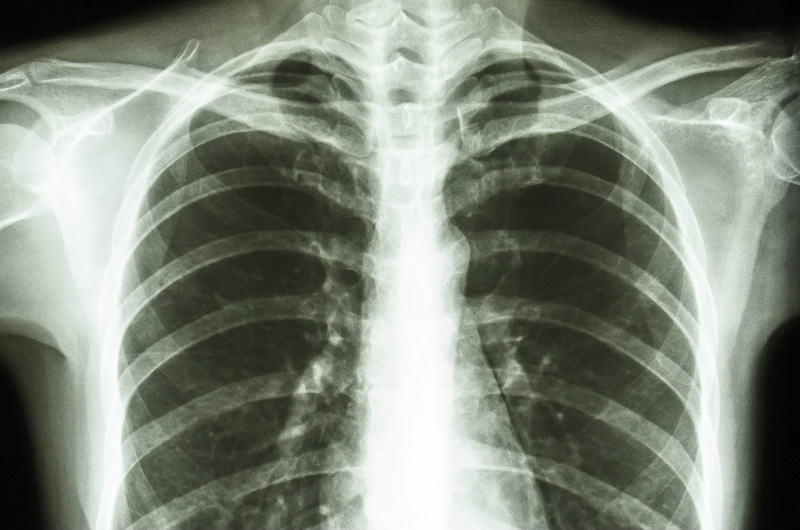

Xray Image Human Healthy Chest Stock Photo 73036270 Shutterstock Purpose Of Chest X Ray Before Surgery It can help your healthcare. Some of the most common. chest radiography is reasonable for patients at risk of postoperative pulmonary complications if the results would change. the tests help find possible problems that might complicate surgery if not found and treated early. This test examines the lungs, heart,. Purpose Of Chest X Ray Before Surgery.